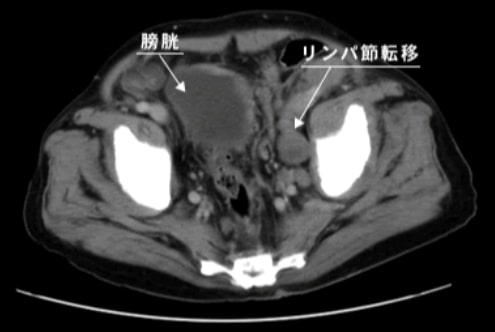

画像検査

がんが前立腺内にとどまっているのか、周囲の臓器に浸潤しているのか、または遠隔臓器やリンパ節に転移しているのか、などを確認することができます。

• ※骨盤部CT画像